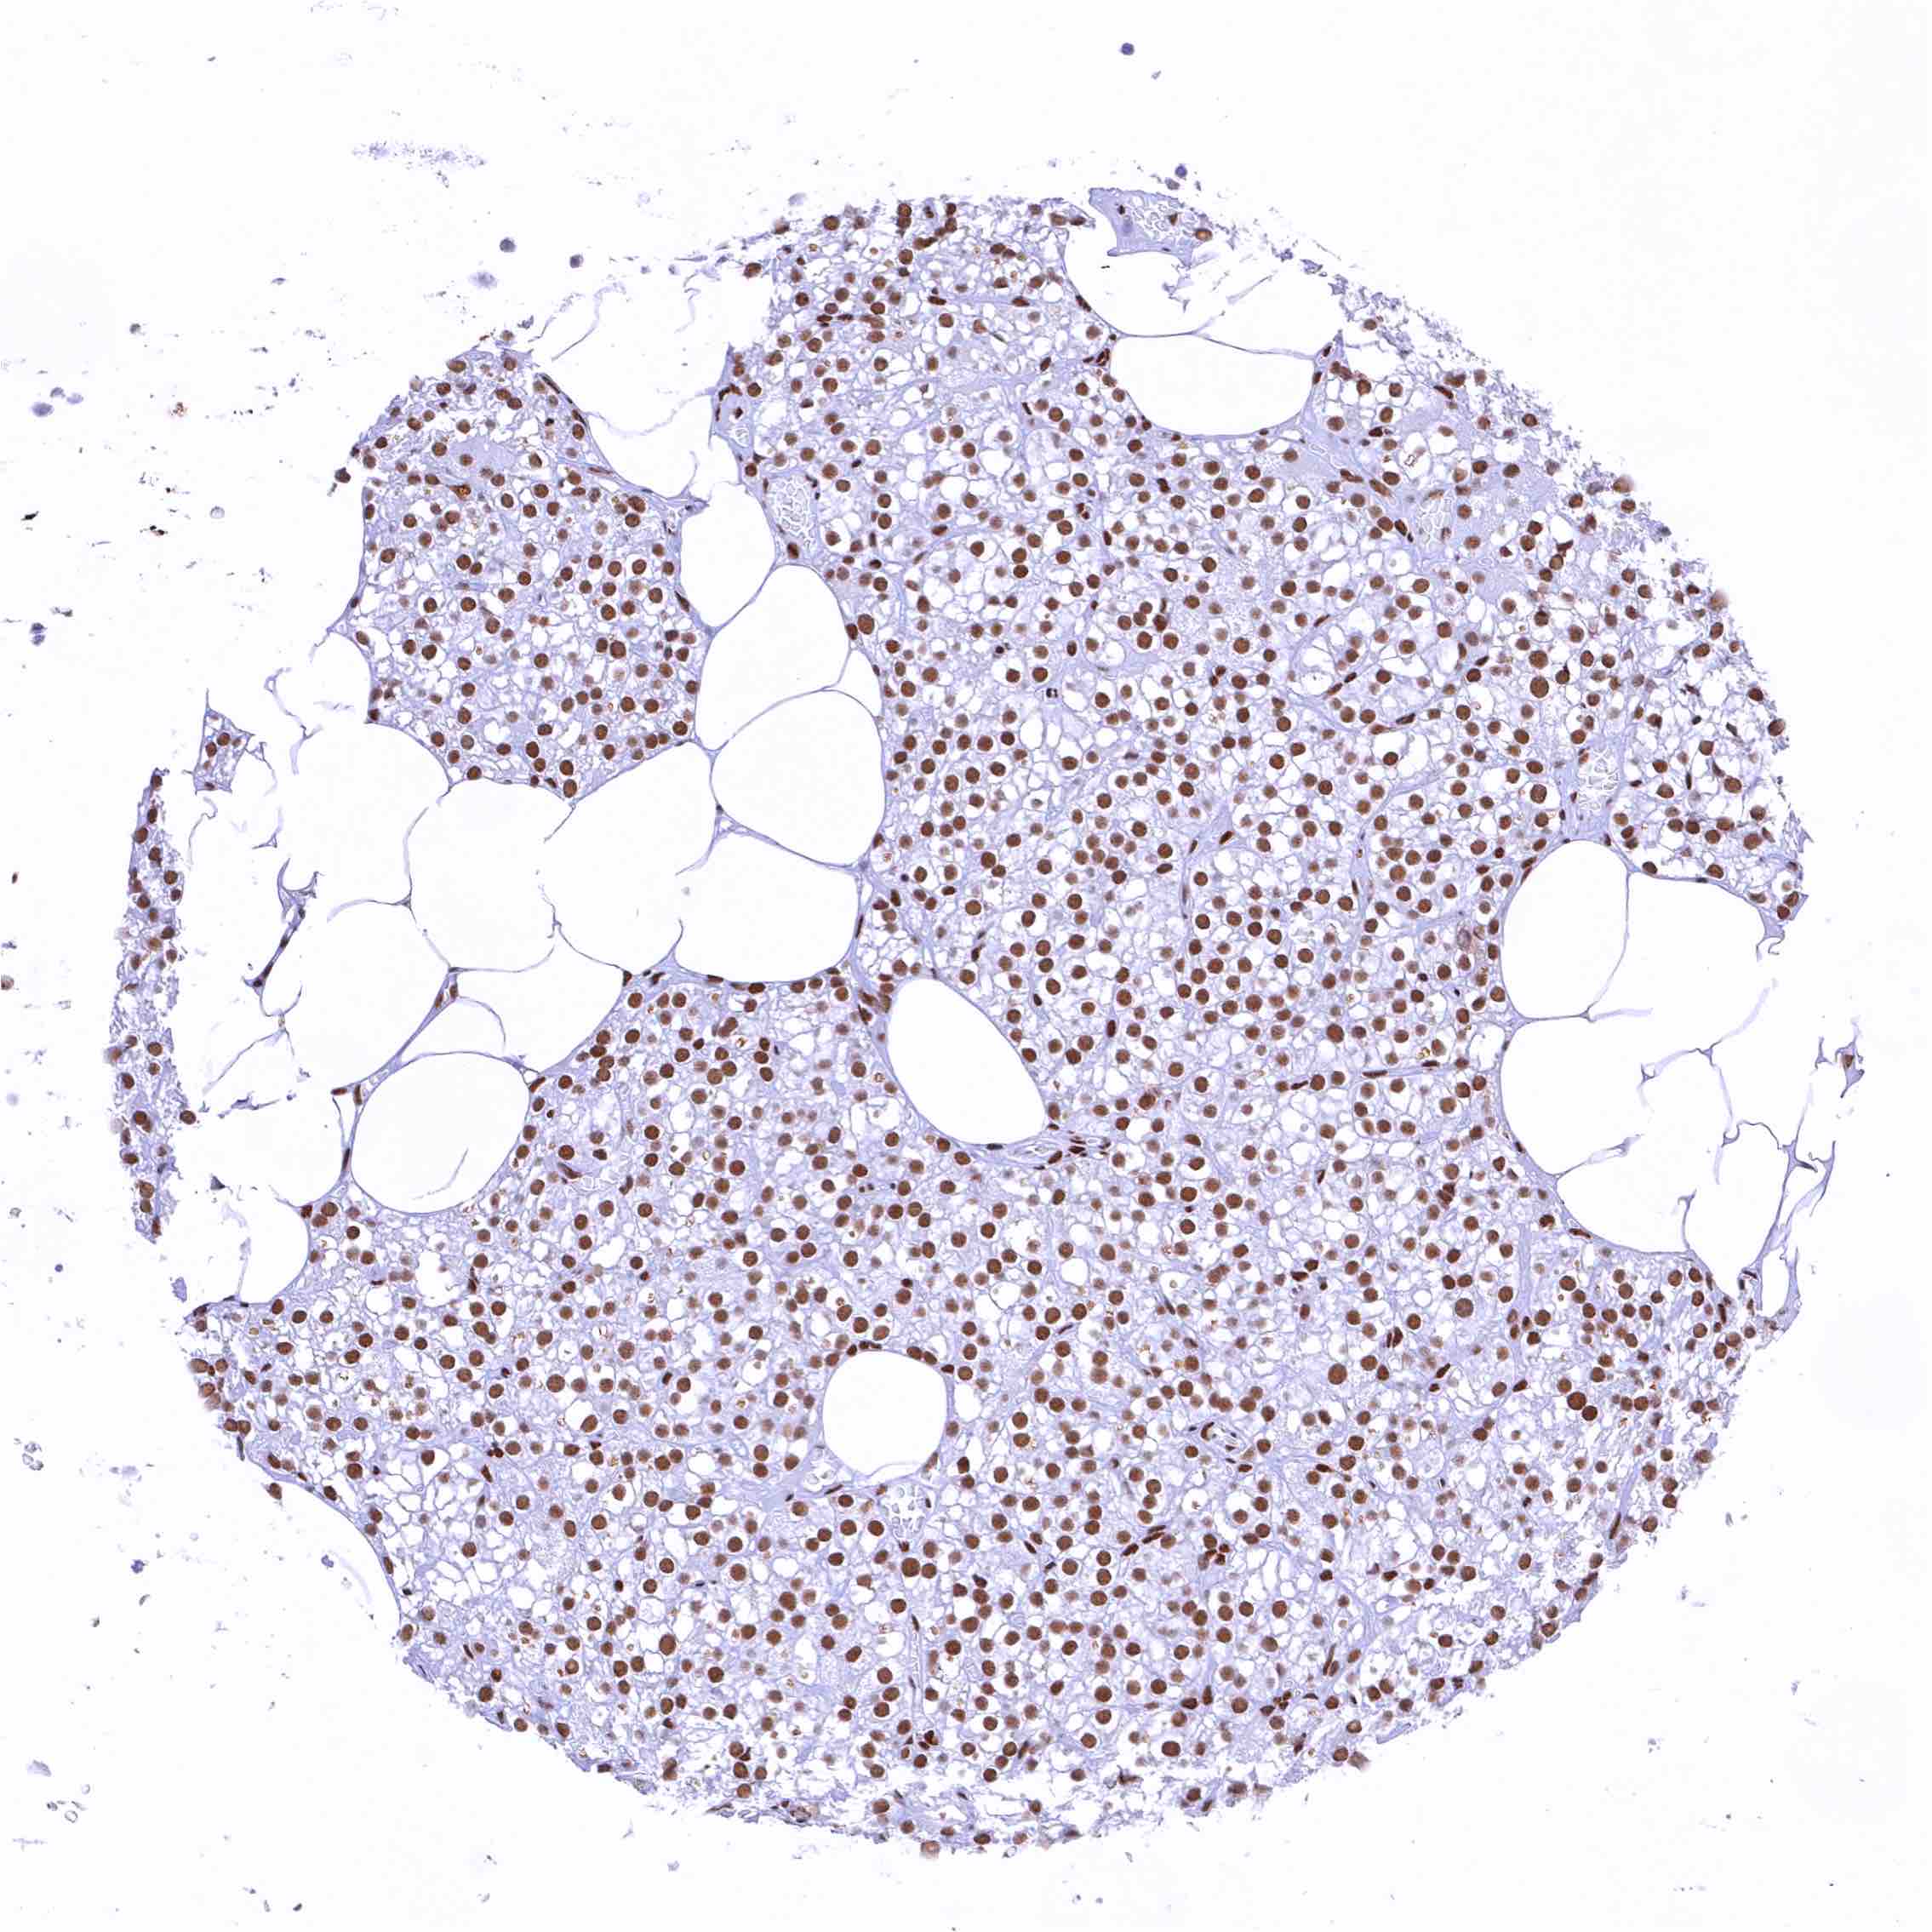

Bone marrow